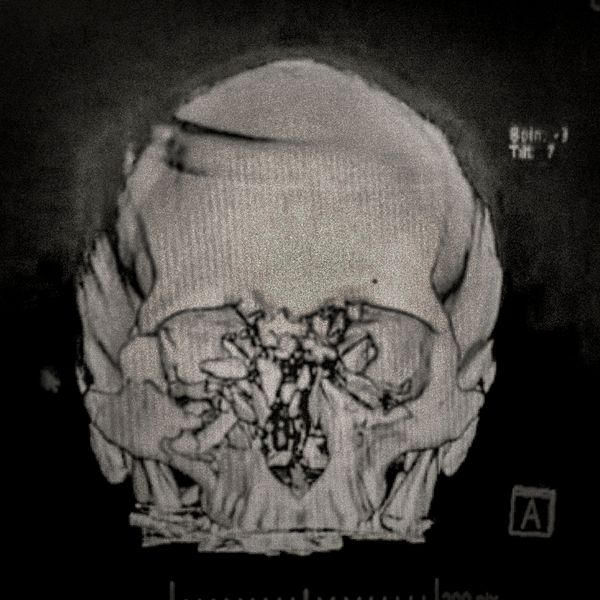

460 people have been seriously injured in their eyes, 34 of whom suffered total loss due to the indiscriminate use of pellets and tear gas bombs by the Carabineros de Chile special forces. The Carabineros fired their rubber bullets and tear gas guns directly into the faces of the protesters during the Chilean social outbreak between late 2019 and early 2020. This figure has made Chile the country with the world record for eye mutilation by state and security forces.

By early March 2020, around 3,838 people had been injured and according to the Chilean Society of Ophthalmologists and human rights organizations, 460 of them ended up with serious eye complications, loss of the eyeball, and also loss of sight. This figure has made Chile a world record for eye mutilation, due to the indiscriminate use of pellets and tear gas bombs by special forces of the Carabineros, who have shot their weapons directly into the faces of the protesters.